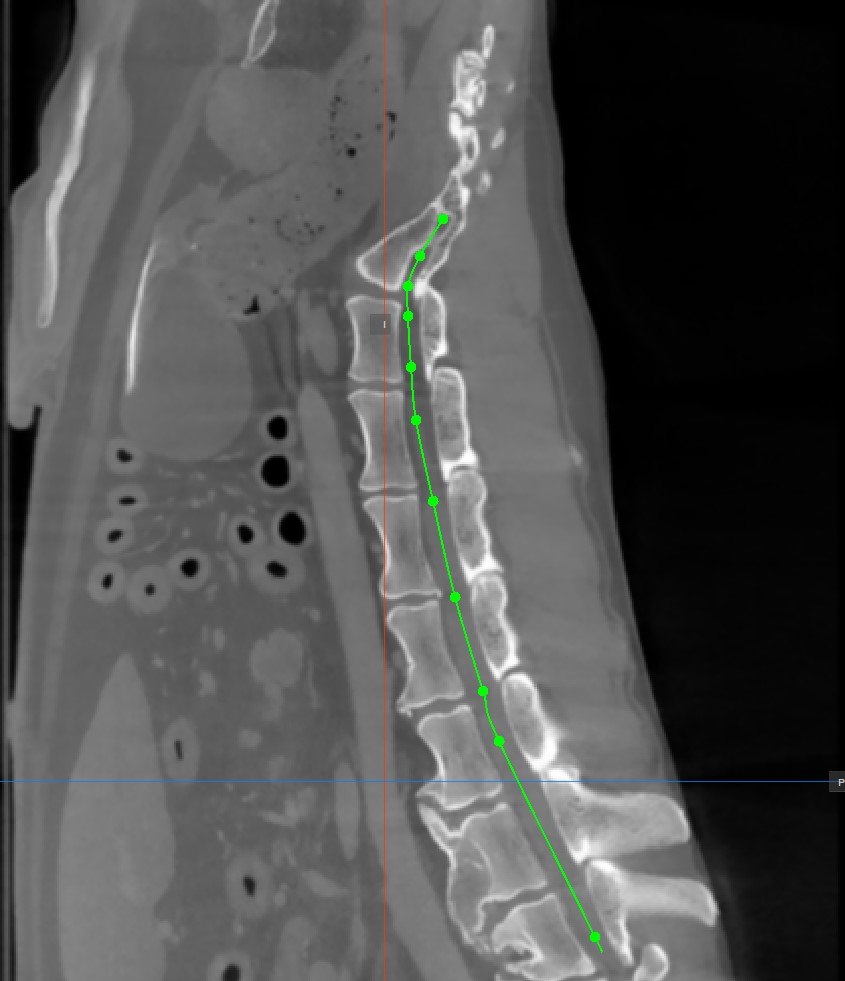

Curved MPR (CMPR) View

Curved MPR, a variation of MPR, creates cross-sectional images along a user-drawn curved path. CMPR can be especially useful when visualizing complex or irregular structures, such as blood vessels or various spinal structures.

The curved MPR straightened view, along with its associated slicers are located on the left side of the viewer, while the standard MPR in all three available planes is located on the right side of the window.

Add Curved Path Points

The Curved MPR requires a user-drawn path in order to generate the cross-sectional images. Select the Add CMPR Point tool located at the bottom section of the CMPR view to draw the required path.

• The points generating the path have to be placed on one of the three available standard MPR viewports on the right side of the window. Choose the most appropriate plane for the requirements.

• At least two points have to be placed on the images in order to generate the path. The CMPR view will be more detailed when more points are used to draw the path.

• To complete the path, toggle the Add CMPR Point tool again, or double-click with the mouse on the image after placing the last point of the path. The path will be marked in green once it’s finalized.

Hovering over the straightened view of the CMPR path will display an orange dot on the path drawn on the MPR images, highlighting the precise location of the cursor.